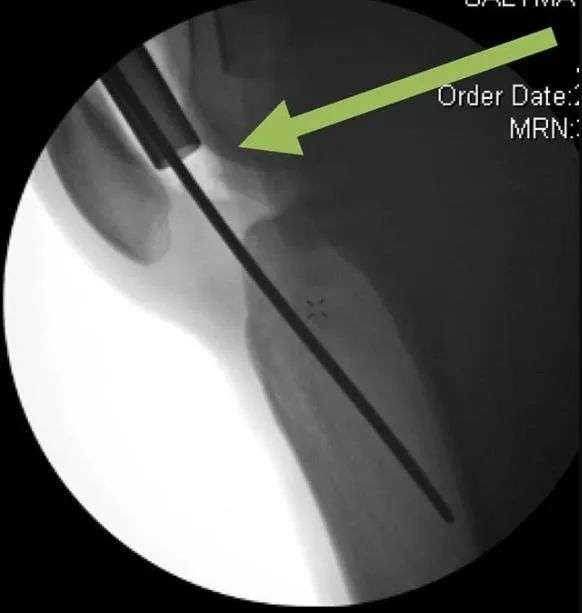

- kapindahan Intraoperative tina leungeun baju pelindung bisa ngakibatkeun karuksakan kartilage jeung struktur dengkul intra-articular (Gambar 17). The leungeun baju pelindung kudu pinuh reinserted.

- Ngadengdekkeun saeutik tina leungeun baju pelindung bisa exacerbate ékstraksi sirah reamer. Fluoroscopy mantuan pikeun ngaidentipikasi masalah. Re-adjustment tina leungeun baju pelindung bakal ngajawab masalah (Gbr. 18)

Gambar 17 Ditarikna leungeun baju pelindung tanpa observasi fluoroscopic bisa ngakibatkeun tatu dengkul

Gambar 18 a Ngadengdekkeun atawa ngadengdekkeun teu kahaja tina casing pelindung bisa ngaganggu panyabutan reamer, sabab sirah reamer bisa macet. b A inspeksi fluoroscopic kalawan koreksi alignment ngamungkinkeun ngaleupaskeun sirah reamer. c Kepala reamer tiasa dicabut upami sirah reamer henteu di tempatna. d The reamer head bisa dicabut lamun reamer head teu di tempatna.